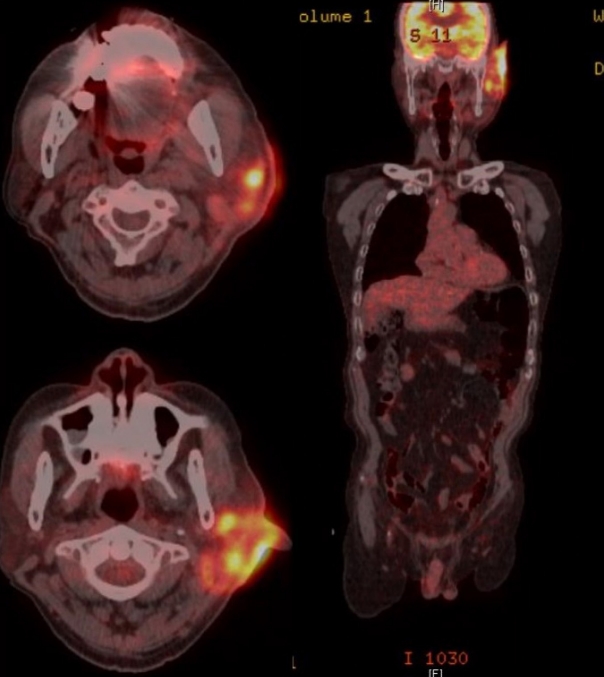

환자 본인의 의사로 타 병원으로 전원 하였고, 본원 최초 내원 두 달 후 타 병원에서 시행한 측두골 자기공명영상에서 좌측 외이도와 이개부 연조직의 부종, 이하선 및 주변 림프절 비대소견으로 염증성 병변과 함께 종양성 상태 의심 소견이 보고되었다(Fig. 4). 재내원 시 병변의 범위는 후이개까지 확장된 악화소견이 관찰되었다(Fig. 2E and F). 환자는 본원에서의 치료 지속을 원하여 양전자컴퓨터단층촬영을 시행하였으며, 좌측 외이도, 이개부 및 이하선을 포함한 불규칙한 과대사성 병변이 관찰되어 악성종양이 여전히 의심되었다(Fig. 5).

NotesAuthor Contribution Conceptualization: Tae Hoon Kong. Data curation: Dong Hwan Kwon. Funding acquisition: Tae Hoon Kong. Investigation: Minheon Kim. Project administration: Tae Hoon Kong. Supervision: Tae Hoon Kong. Visualization: Minheon Kim. Writing—original draft: Joo Hyung Lee. Writing—review & editing: Joo Hyung Lee, Tae Hoon Kong. Fig. 1.Initial ear findings and audiometry of the patient on first visit. A: Initial skin and soft tissue inflammation (post start of treatment day 21). B: Pure tone audiometry shows the air-bone gap (35 dB) of the left ear (red: right ear, blue: left ear). Fig. 2.Skin and soft tissue inflammation. Redness and swelling aggravated during antibiotic therapy and daily wound care. A: Post start of treatment day (PTD) 40. B: PTD 46. C: PTD 64. D: PTD 69. E: PTD 93. F: PTD 99. Fig. 3.CT of neck. 3.4×2.3×2.9 cm sized enhancing mass-like lesion at left external auditory canal and left ear auricle with enlarged lymph nodes at periparotid region. A: Coronal view. B: Axial view. C: Axial view of enlarged lymph node. Fig. 4.MRI of temporal bone. Subepithelial soft tissue thickening in the external auditory canal (cartilaginous portion) and auricle aggravated during antibiotic therapy and daily wound care. A: Post start of treatment day (PTD) 16, T2 weighted image (T2WI) axial. B: PTD 16, T1 weighted image (T1WI) coronal. C: PTD 96, T2WI axial. D: PTD 96, T1WI coronal. Fig. 5.PET-CT scan (torso). Left external auditory canal and left ear auricle, periauricular area, left parotid gland involving irregular hypermetabolic lesion was seen. Fig. 6.Histological findings. Polymorphous lymphoid cells infiltrate lacing cytologic atypia on PTD 112 compared to previous study. A: Post start of treatment day (PTD) 16, ear, Lt (hematoxylin and eosin [H&E], ×200). B: PTD 24, ear, Lt (H&E, ×200). C: PTD 58, parotid gland, Lt (H&E, ×200). D: PTD 112, ear, Lt (H&E, ×200). E: PTD 112, ear, Lt (CD3, ×100). F: PTD 112, ear, Lt (Epstein-Barr virus in situ hybridization, ×100 view). Fig. 7.Skin and soft issue inflammation has shown much improvement and epithelization of the wound was achieved after six months of treatment (post start of treatment day 174). Table 1.Differential diagnosis of chronic active Epstein-Barr virus of T-cell type REFERENCES1. Wauchope J, Dorris CB, Smith CP, Hanna B. Chronic active Epstein-Barr virus: A multidisciplinary approach. BMJ Case Rep 2020;13(12):e236287.